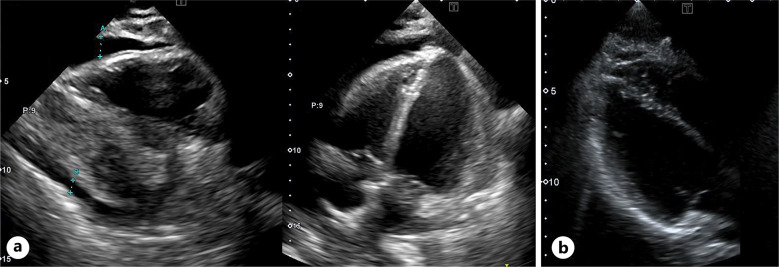

Case presentation: A 31-year-old female with NTRK1 fusion-positive breast cancer presented to our hospital with dyspnea and orthopnea 21 days after initiating entrectinib therapy (600 mg/day orally). Transthoracic echocardiography revealed circumferential pericardial effusion with diastolic right atrial and ventricular collapse. Consequently, she was diagnosed with pericarditis complicated by cardiac tamponade, and pericardiocentesis was performed. Cardiac tamponade resolved after discontinuation of entrectinib and initiation of corticosteroid therapy. Subsequently, larotrectinib (200 mg/day orally) was initiated.